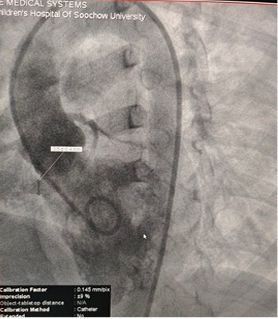

Los hallazgos del eco preoperatorio:

Diámetro base: ~ 6,1mm con múltiples puntos de salida

Tejido similar a una membrana observado sobre el defecto

Doppler color: flujo de derivación de izquierda a derecha

Diagnóstico: VSD perimembranoso

Desafío: múltiples salidas de tejido de membrana frágil

Selected MemoSorb ABFDQ-II 9 occluder based on intraoperative angiography and echocardiographic assessment.